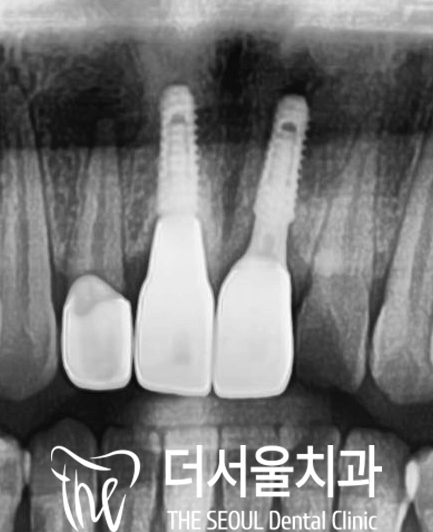

엑스레이 사진을 보면

왼쪽이 더서울 성남 치과

오른쪽이 타원 보철인데

앞서 말씀드린 이머전시 프로파일의

차이가 있는 것이 보여집니다.

다른 곳에서 하신 임플란트와 크라운의

연결 지대주에 문제가 있는 것 같습니다.

굴곡진 부분이 보이시나요?

11번 치아는 매끄러운

라인으로 이어지는 반면에

21번은 풍융도가 큰 라인으로

이어지고 있습니다.

이곳이 부드럽게 이어지지 않아

잇몸에 염증이 생겨

발적과 부종이 있습니다.